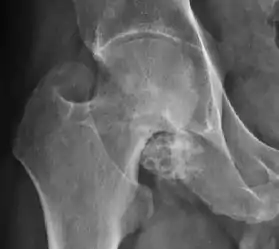

Synovial chondromatosis can be confidently diagnosed by X-ray when calcified cartilaginous chondromas are seen. However, other synovial proliferative processes, such as pigmented villonodular synovitis, require MRI for accurate diagnosis, although noncalcified synovitis can be suspected in radiographs by indirect signs, such as soft tissue swelling and/or erosions in the femoral head, femoral neck, or acetabulum (Figure 7).[1]

Figure 7:

Figure 10:

In synovial proliferative disorders, MRI demonstrates synovial hypertrophy. In the case of PVNS, characteristic foci of low signal intensity related to hemosiderin deposition are better seen on gradient echo T2* images (Figure 7). In the case of synovial osteochondromatosis, the synovial hypertrophy is accompanied by intermediate signal cartilaginous loose bodies and/or low signal calcified loose bodies.[1]